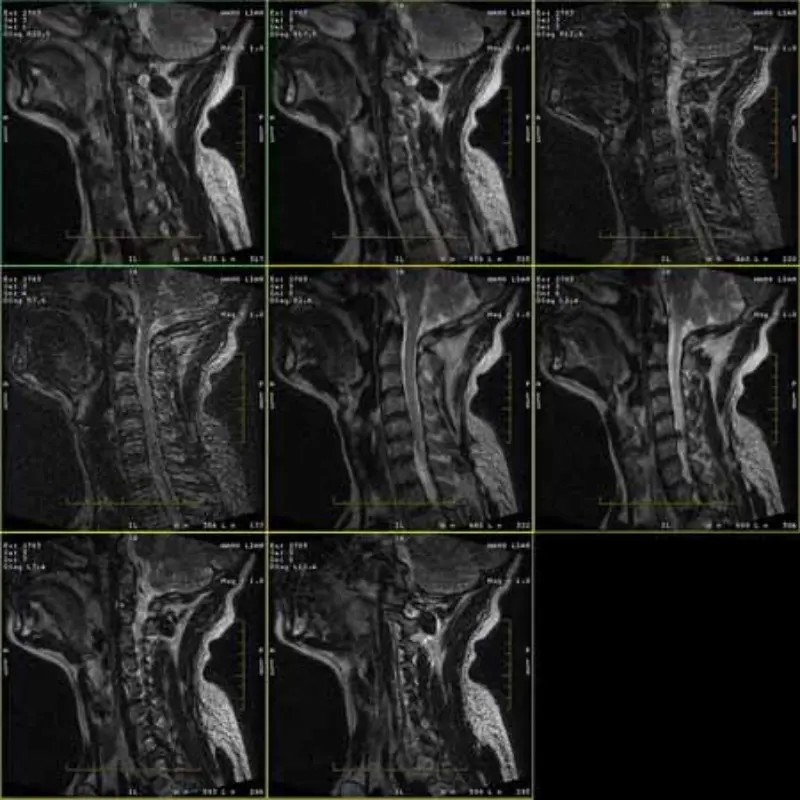

FRFSE және GRE протоколдарының кескіндері елес болады және кейде төмен SNR кескіндері бір серияда пайда болады. Бірақ SE протоколының кескіндері қалыпты.

Қосымша суреттерді қараңыз.